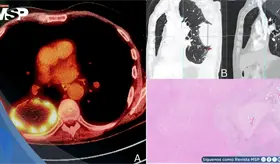

El estudio histológico confirmó un adenocarcinoma mucinoso de células en anillo de sello de vejiga con invasión muscular y diseminación metastásica pulmonar y ósea.